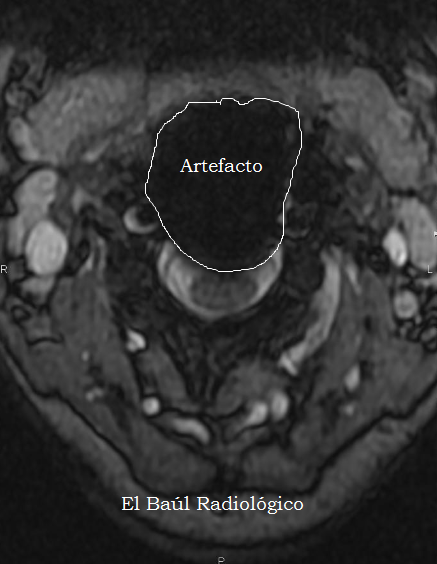

FIGURA 7) Aspecto ovalado hipointenso de un implante intersomático visto en proyeccción axial, FSE-T1.

(Oval hypointense appearance of an intersomatic implant seen in axial proyeccción, sequence FSE-T1).